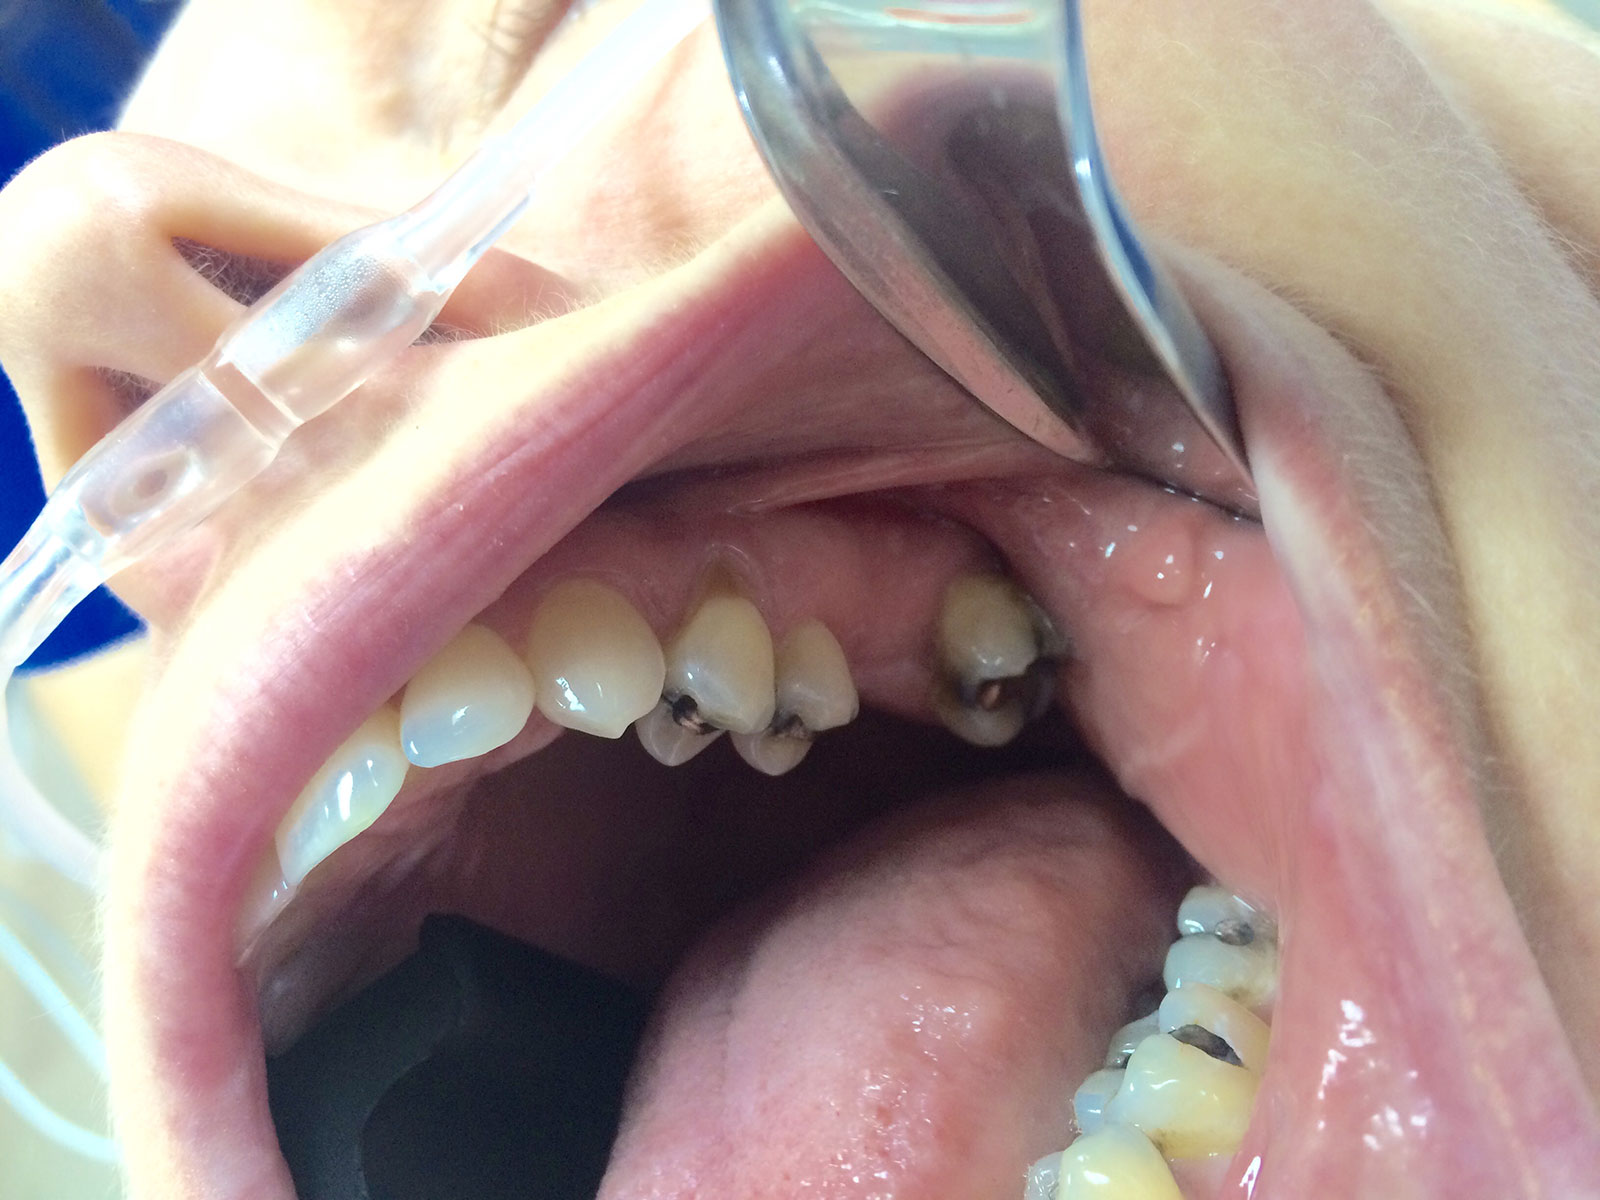

Sinus Grafting Procedures

A sinus grafting procedure, also known as a sinus augmentation, is for patients who have insufficient natural bone in the areas where dental implants are needed. They are long lasting, strong and sturdy, and fit and function like natural teeth. The procedure involves adding bone, either your own natural bone from another part of the body, from a donor or made of processed or synthetic bone material, and placing it below the sinus so that the implants can be placed. After the bone has healed and developed, usually around four to 12 months, the dental implants can be placed.

The photos on this website are from real surgeries performed by Dr. Ulloa. Due to the

graphic nature of the images and content, viewer discretion is advised.